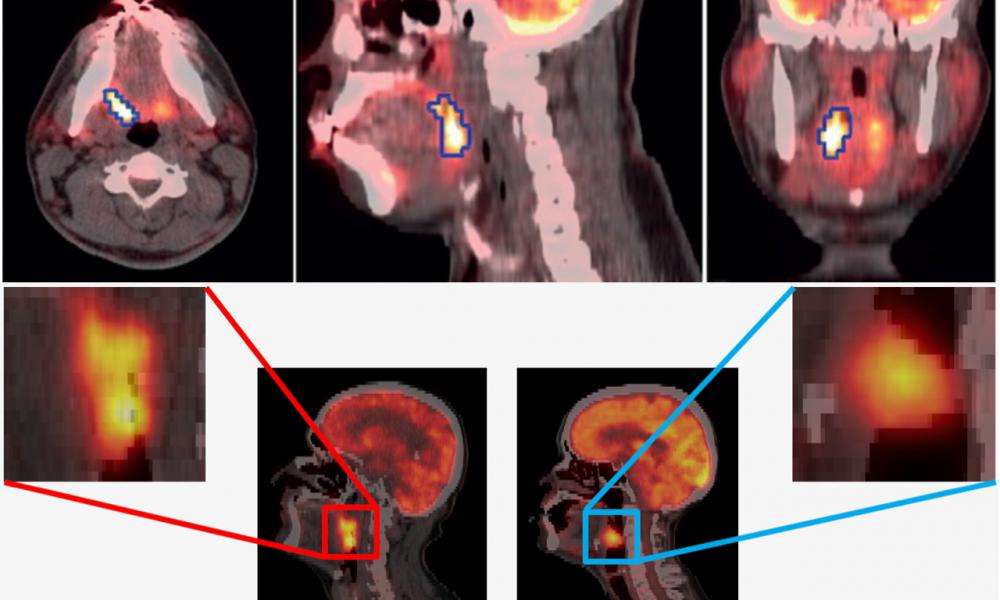

- Quantitative PET imaging methods for enhanced diagnosis, prognosis and treatment response assessment of cancer patients (e.g. prostate cancer, lymphoma, lung cancer, …)

- AI and Radiomics methods as applied to PET and SPECT imaging of cancer